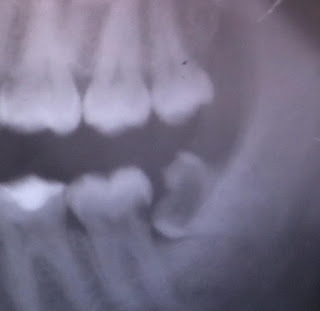

| Posisi gigi yang miring dan menghantam gigi sampingnya. |

| Atas-Tengah: Gigi kiri bawah yang pecah jadi 2 bagian. Bawah: Gigi kanan atas yang bagian mahkotanya udah keropos. |